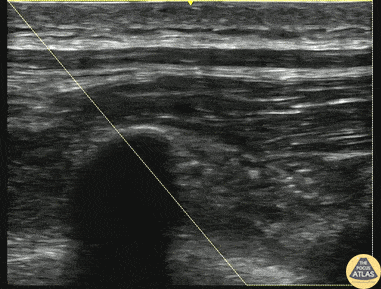

60s M presented after bicycle crash, and was found to have multiple unilateral rib fractures. To aid with pain control, an erector spinae plane block was placed using bupivacaine. The block is shown here, with the needle approaching in plane from the right of the screen (inferior). The first few seconds of the clip show the anatomy from lateral to medial, with the posterior rib with associated pleura seen, before the more medial transverse process is seen, without associated pleura. The target of anesthetic spread is the fascial plane (*) between the transverse process and the overlying erector spinae muscle. The second half of the clip shows administration of anesthetic with spread visible along the target fascial plane. Dr. Matthew Riscinti, Fellowship Director Denver Health Ultrasound